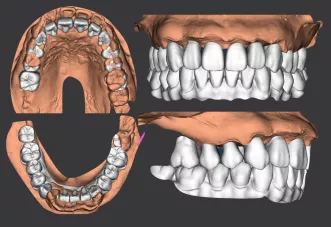

· 侧貌美学预告后,确定了上前牙矢状面前后向的位置关系,中切牙在矢状面上的位置变化:将唇倾的上前牙直立,上中切牙角度减小12度,切端内收8mm。

· 根据正侧貌美学预告,确定了咬合重建最重要的起点,上中切牙三维位置 ,𬌗面参看(FH平面)眶耳平面,并指导全口数字化排牙。

· 制作放射导板,进行数字化导板设计。

· 上下各计划植入6颗种植体。其中14、24种植体倾斜植入,15、25经牙槽嵴顶上颌窦提升植骨,其余牙位无需植骨。

种植体位置设计,可见上前牙唇侧骨量过丰满,需适量去骨。同时上下颌均需要截骨处理。

· 上下颌士卓曼360数字化导板 +预成临时修复体设计图。

· 士卓曼360导板包括:骨支持的基部导板 、牙支持的辅助导板 、就位于基部导板的种植导板 以及就位于基部导板的预成临时修复体组成。

· 上下颌计划行即刻种植,各植入六颗straumann钛锆种植体并行即刻修复。